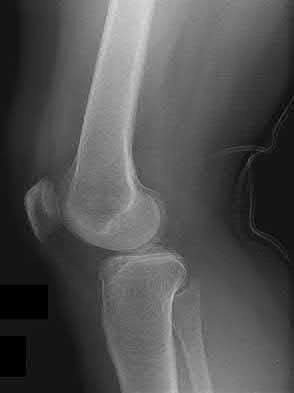

3. # Which of the following is not an appropriate implant for treatment of the fracture seen in Figure A?

5. Sliding hip screw Corrent answer: 5

The image shows a reverse obliquity intertrochanteric hip fracture.

According to the referenced article by Haidukewych et al, unstable peritrochanteric hip fractures have a worse outcome (failed in 9/16 cases) if treated with a sliding hip screw. Two additional factors that were found to have a strong correlation with postoperative failure (nonunion, loss of reduction) were poor reduction and poor implant placement. In this study, fixed angle devices were superior. Intramedullary fixation has the added advantage of a shorter lever arm and less potential for fracture collapse and limb shortening.

The IMN also acts as a medial buttress.

According to Sanders et al, the dynamic condylar screw (DCS) can also be used in subtrochanteric models, but should not be used if extensive comminution is seen, as they reported a high failure rate with DCS in these fractures if highly comminuted. They report a 77% overall union rate with this device.